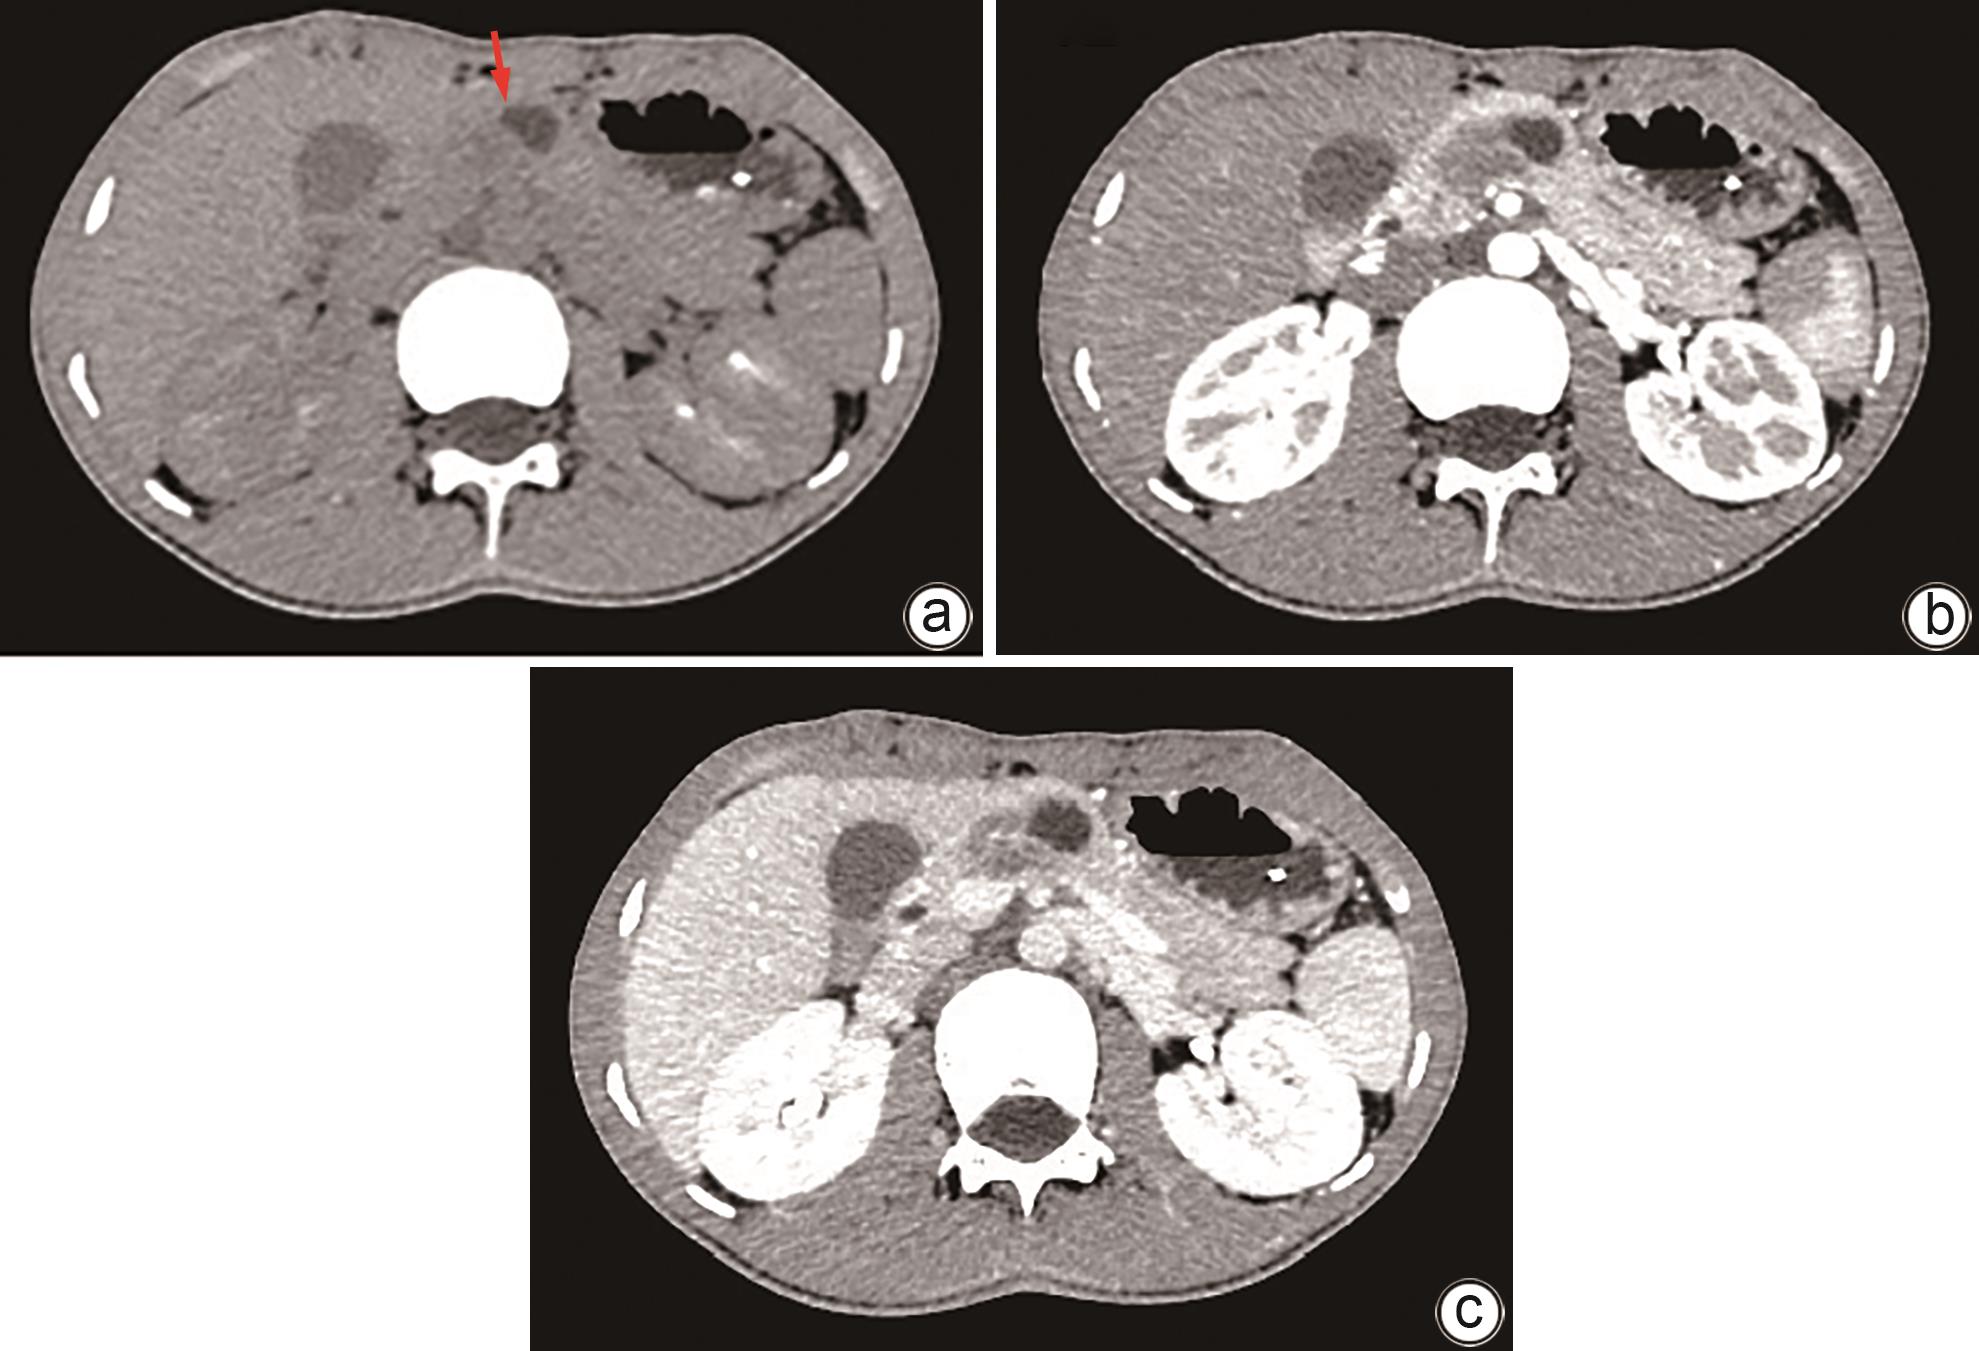

Imaging features and therapeutic strategies for lethal iatrogenic hemobilia

Chen WANG, Min WANG, Ke ZHANG, Jinxing ZHANG, Li LIU, Zhining FAN

2024, 40(10): 2070-2074. DOI: 10.12449/JCH241022

Abstract(997) HTML (354) PDF (2026KB)(80)

Abstract:

Objective  To investigate the imaging features and pathogenesis of lethal iatrogenic hemobilia (LIH) and the value of transarterial intervention in the treatment of LIH.  Methods  A total of 269 patients with upper gastrointestinal bleeding who were admitted to The First Affiliated Hospital of Nanjing Medical University from August 2009 to July 2023 were enrolled, among whom 24 had a confirmed diagnosis of LIH and received treatment, and a retrospective analysis was performed for the clinical data of these 24 patients, including the iatrogenic causes, angiographic findings, and arterial interventions of LIH. Among the 24 patients, 23 received transarterial embolization (TAE) with gelatin sponge particles and coils, and 1 received a covered stent for isolation. The main criteria for assessing treatment outcome included the technical success rate of surgery, procedure-related complications, and long-term clinical follow-up.  Results  Among the 24 patients with LIH, 12 had LIH caused by interventional procedures, and 12 had LIH caused by hepatobiliary and pancreatic surgery. The main clinical manifestations included a significant reduction in blood pressure or a persistent reduction in hemoglobin in 13 patients and upper gastrointestinal bleeding in 18 patients. Among the 24 patients, 2 developed symptoms during surgery, 4 developed symptoms within 24 hours, and 18 developed symptoms after 24 hours. Angiography showed a positive bleeding rate of 100% (24/24), and imaging findings included pseudoaneurysms in 15 patients, hepatic artery truncation in 3 patients, extravasation of contrast medium in 5 patients, and hepatic arteriobiliary fistula in 3 patients. Among the 24 patients, 23 received TAE and 1 received stent implantation. Successful hemostasis was achieved for 23 patients, with a technical success rate of 95.8% (23/24). Four patients developed hepatic necrosis and abscess after TAE, and there was no rebleeding or recurrence after hemostatic treatment.  Conclusion  Various iatrogenic injuries may result in LIH with diverse clinical and imaging findings, and integrated diagnostic imaging combined with transarterial intervention is the best effective life-saving measure for LIH.